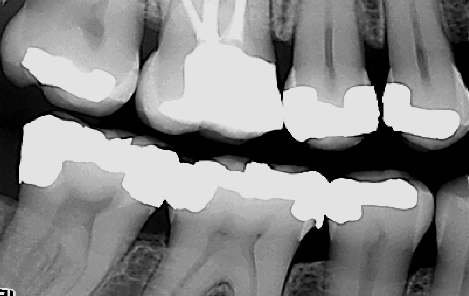

Derfor må tannlegen også vurdere behovet for å ta røntgenbilder i forbindelse med undersøkelsen. Røntgenbilder brukes for å diagnostisere sykdommer i de deler av tennene som ikke er synlige i munnen. I tillegg kan de avdekke patologi i kjevene. Eksempler på slike sykdommer kan være hull under gamle fyllinger eller kjevecyster. I tillegg kan røntgenbilder tatt over flere år sammenlignes. Slik kan man vurdere hvorvidt en tilstand (for eksempel et begynnende hull) har utviklet seg eller ikke.

Det finnes forskjellige former for røntgenbilder. Ved en regelmessig undersøkelse er det vanligvis såkalte bitewings som benyttes. Bitewings gir tannlegen informasjon om blant annet hull i tennene, begynnende hull og kvaliteten til gamle fyllinger. De kan også si noe om tennenes feste og avdekke tegn til periodontitt (tannløsningssykdom). Ved behov kan bitewingbildene måtte suppleres med andre småbilder (for eksempel rotbilder) av avgrensede områder.

Røntgenbilder viser blant annet begynnende hull, behandlingskrevende hull, gamle fyllinger og tennenes benfeste